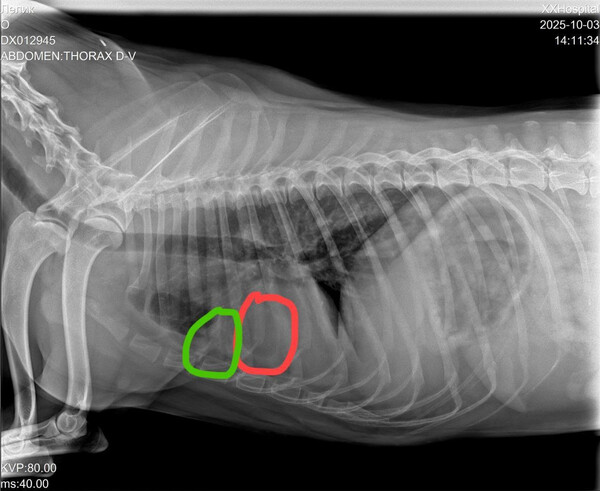

Просим финансовой помощи для песика  Лёлика https://vao-priut.info/load/dogs/sectord/ljolik_d_139/8-1-0-526 (бывшего жителя Кожуховского приюта, сейчас живет на передержке), который страдает заболеванием лёгких. На здоровье не жаловался, а тут стал кашлять и хрипеть при нагрузке, хотя ему только 7,5 лет.  Рентген лёгких выявил два подозрительных уплотнения.

Для постановки диагноза и лечения необходимы КТ и бронхоскопия, так называемый БАЛ и обязательные анализы и обследования.  1 ноября  в Ветсити (чек и выписка прилагаются) было сделано КТ с контрастом и анализы.